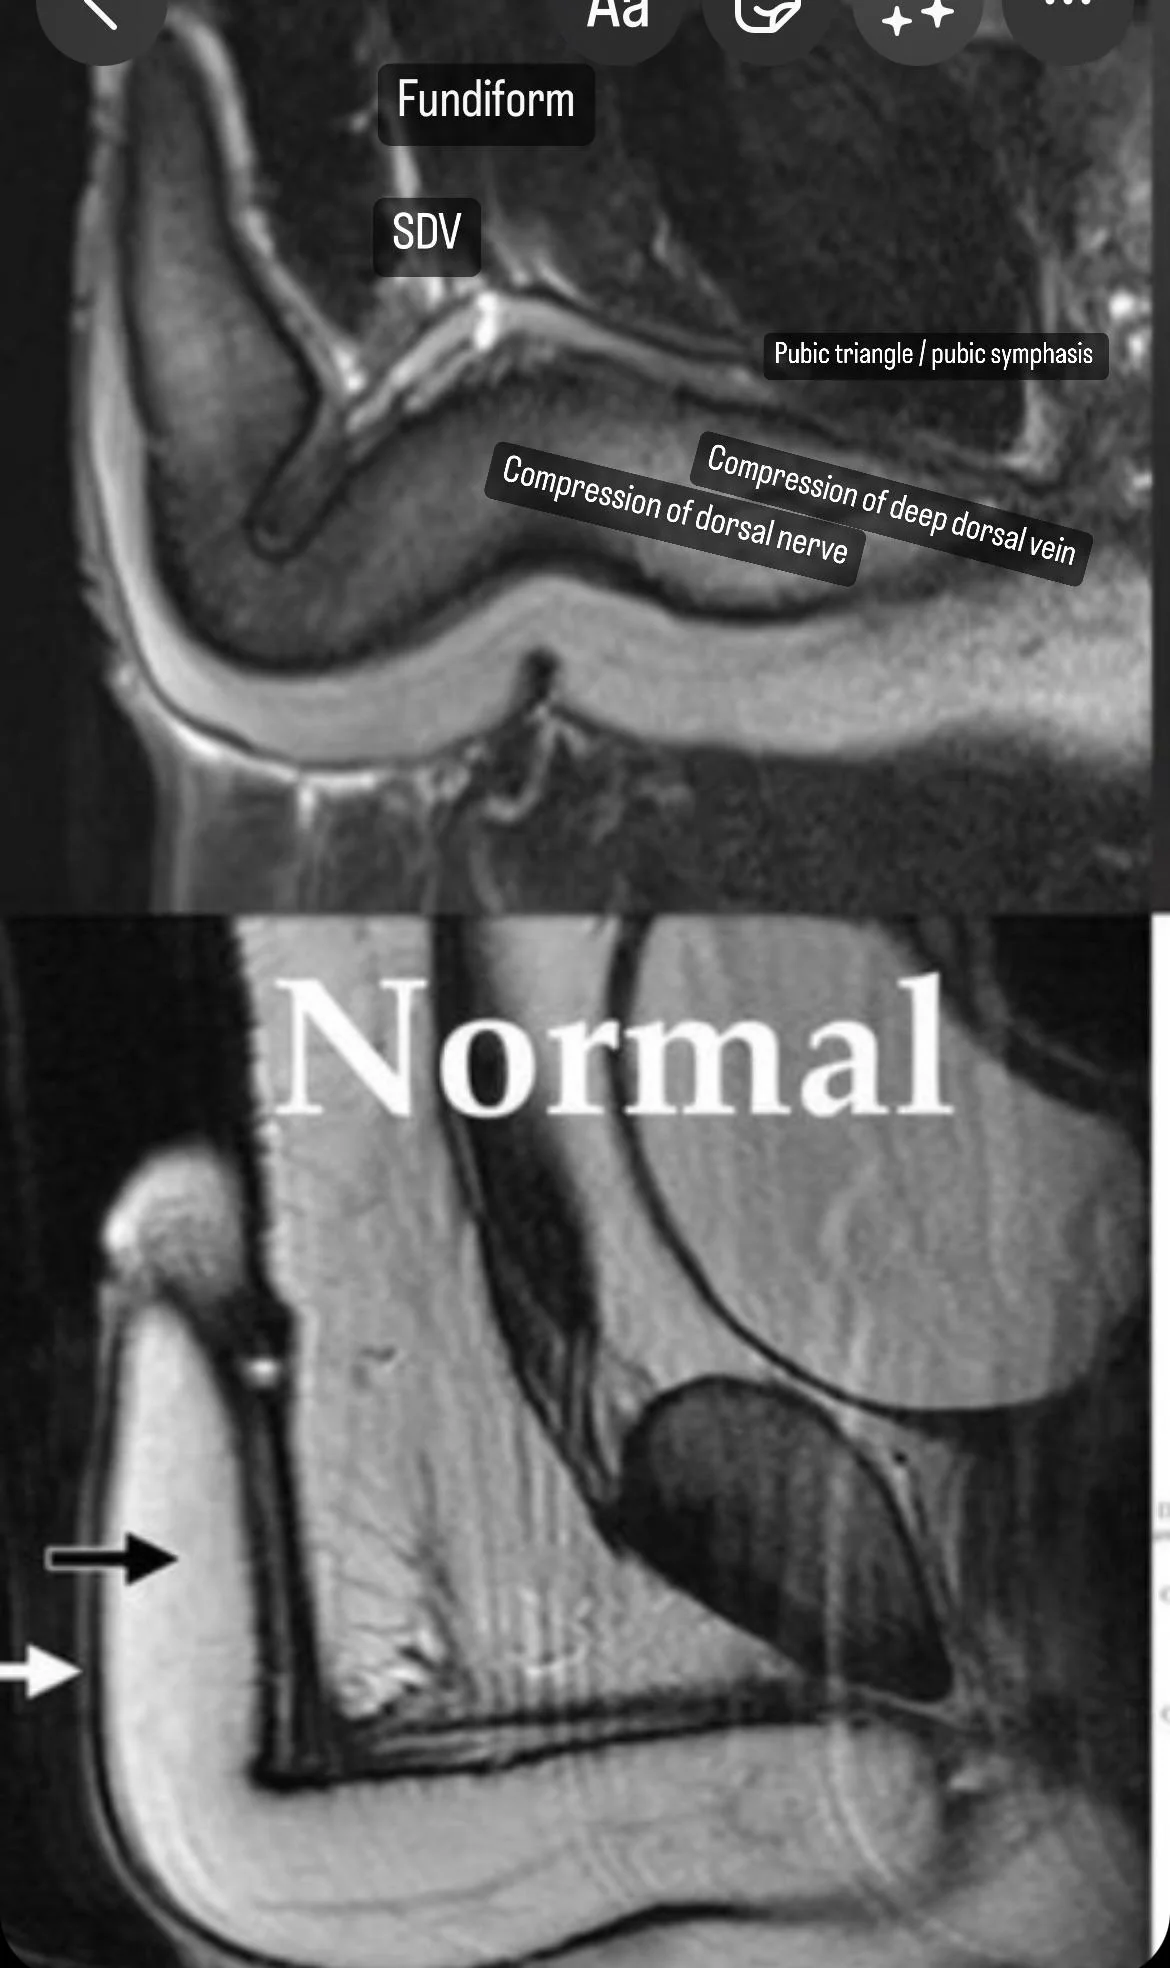

Челики на зарубежном редите по сабжу делали мрт чего-то (я так и не понял какой зоны) с контрастом, у них показало такое.